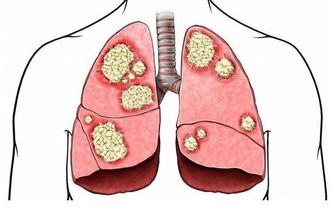

濫用抗生素有可能破壞腸道先天免疫力,這也是引起耐抗生素細菌感染的原因。埃里克·帕爾默領導的紐約“斯隆·凱特林癌症研究所”的研究人員試驗後發現,這是一種廣泛使用抗生素導致的並發症,將使患者的身體健康受到更大傷害。